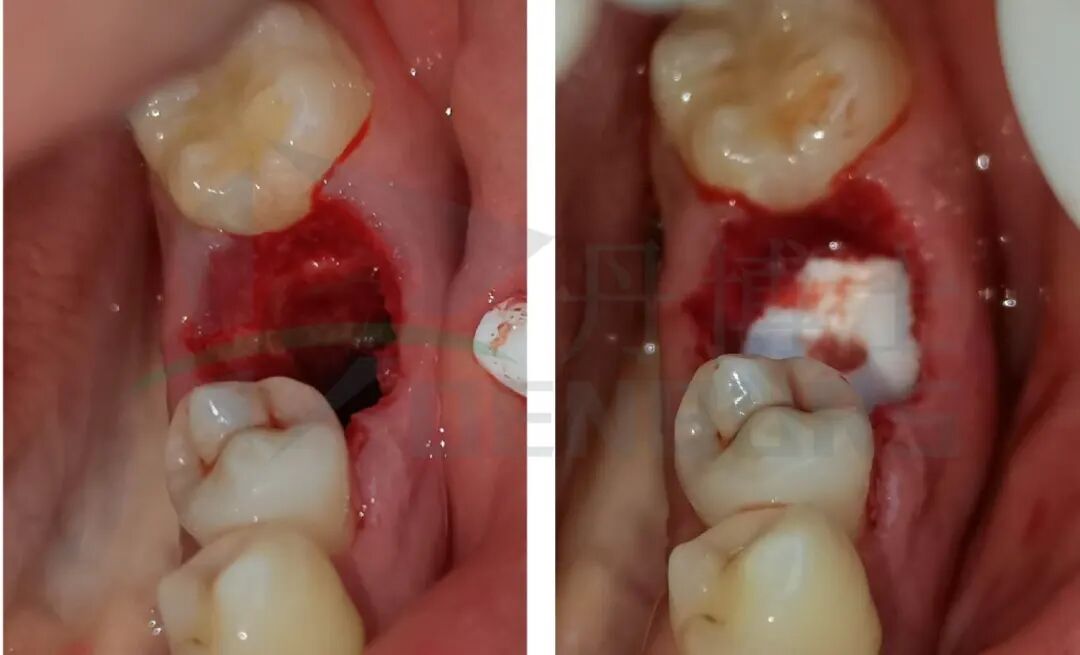

手术过程

死髓牙拔除案例-03.jpg

1、用破冠车针破冠槽 ,取下烤瓷冠。

死髓牙拔除案例-04.jpg死髓牙拔除案例-05.jpg

2、用丹博士C33L.317.012拔牙车针将冠根分为近中、远中两部分,牙梃将近远中根拔除。

死髓牙拔除案例-06.jpg

3、牙槽骨复位后,填塞胶原海绵,创口对位缝合。